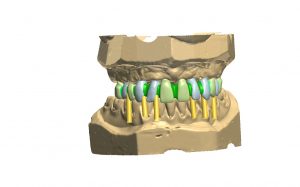

Agunos de nuestros trabajos

A continuación mostramos algunos de nuestros trabajos antes y después del tratamiento.

Rehabilitacion oral con prótesis convencional: Prótesis fija

Rehabilitacion oral con prótesis convencional: Prótesis fija

Rehabilitacion oral con prótesis convencional: Prótesis mixta